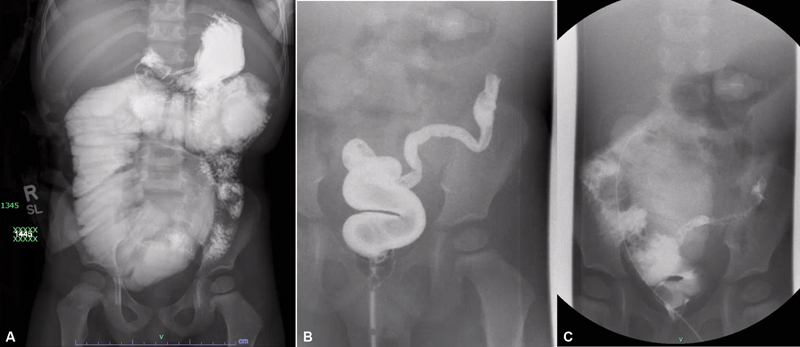

Concomitant presentation of jejunal atresia and Hirschsprung's disease is rare and places children at high risk for developing short bowel syndrome and parenteral nutrition dependence, which can affect the feasibility/timing of pull-through. A patient was born with jejunal atresia with a delayed diagnosis of Hirschsprung's disease. After several procedures and bowel resections, the patient was ultimately left with an end jejunostomy and long Hartman's pouch with short bowel syndrome, dependent on parenteral nutrition. The patient initially presented to our institution at age 2 with failure to thrive secondary to an obstructed/dilated jejunostomy and mild enterocolitis of their defunctionalized segment. The patient subsequently underwent completion of subtotal colectomy and revision of jejunostomy utilizing a serial transverse enteroplasty to manage the dilated bowel and gain length. The patient was able to wean off parenteral nutrition and achieve nutritional autonomy by age 5. Following this, the patient was able to undergo an ileoanal pull-through. After the pull-through, the patient was able to pass stool independently and suffered no major complications to date. Serial transverse enteroplasty can be successfully utilized in patients with a history of Hirschsprung's disease and jejunal atresia to achieve nutritional autonomy and ultimately reestablish gastrointestinal continuity with pull-through.

Abstract Image